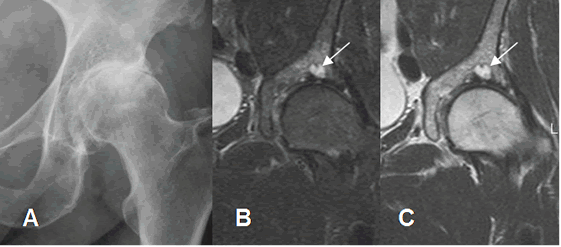

Fig 146. Artropatía degenerativa.

A: Rx AP. Cambios degenerativos con disminución y esclerosis del espacio articular. Alteración femoral, por pinzamiento tipo cam.

B: RM coronal en STIR y C: RM coronal en T2. Quiste subcondral en el acetábulo y osteítis asociada.